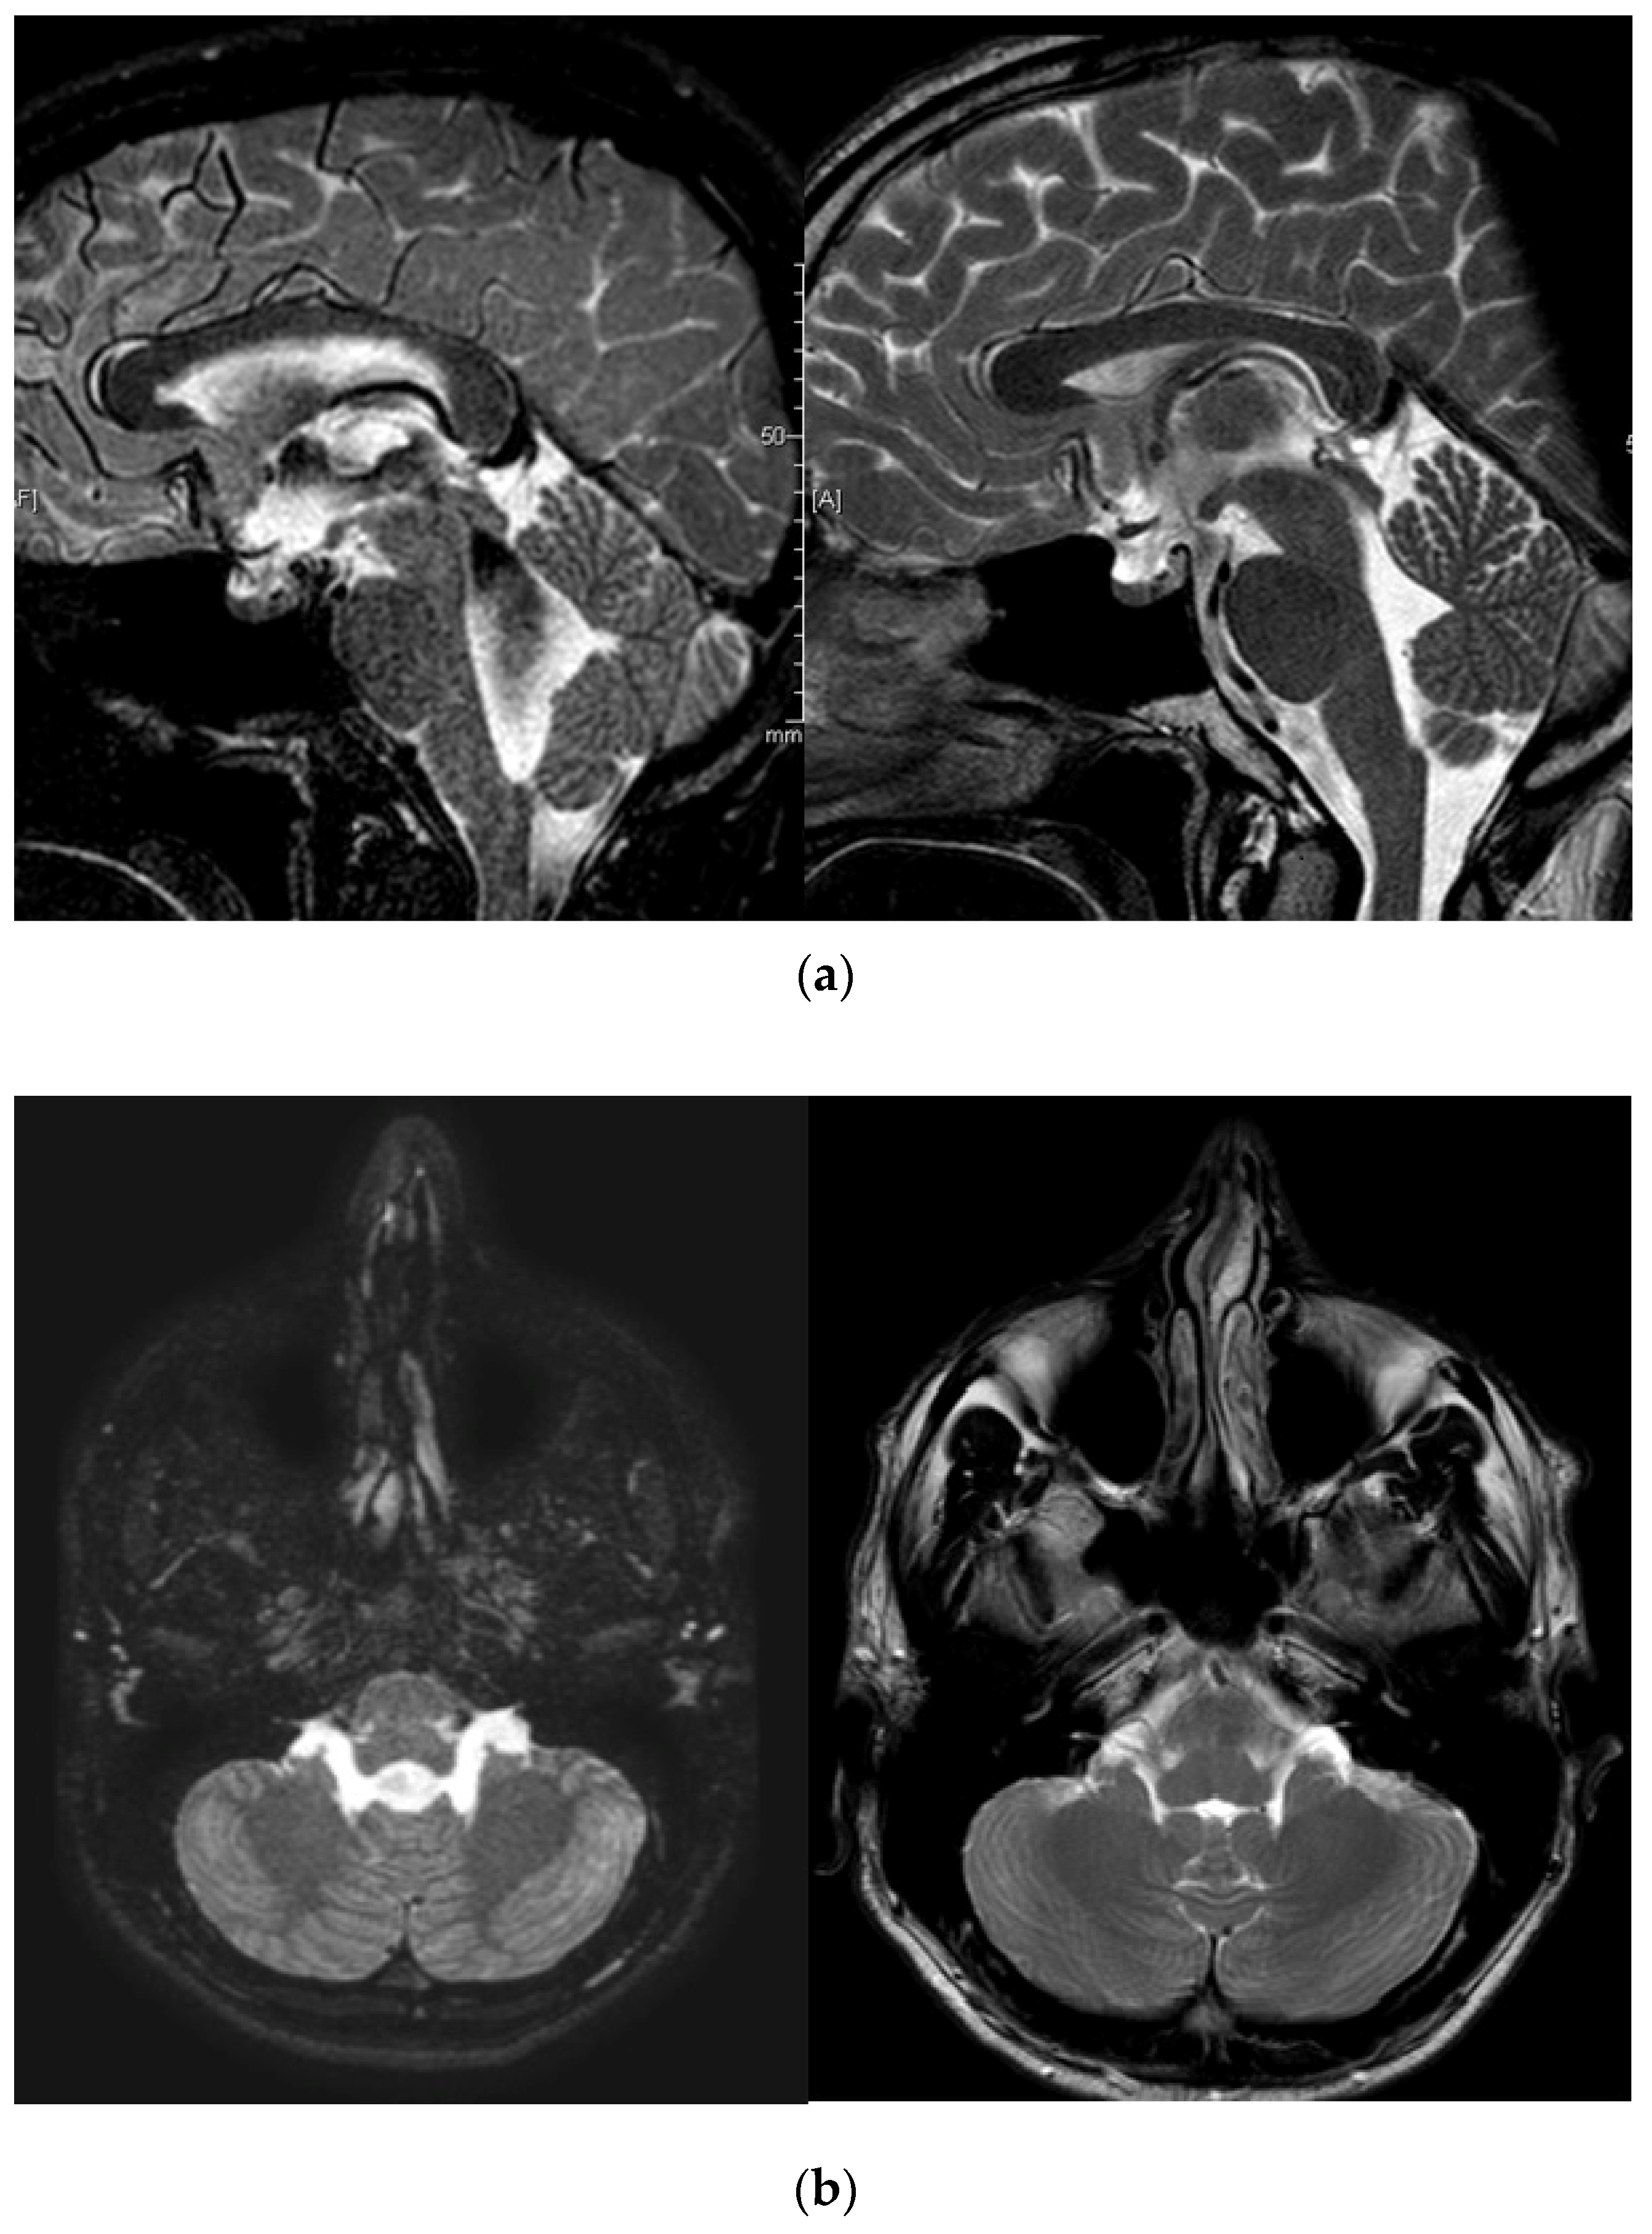

Case Report